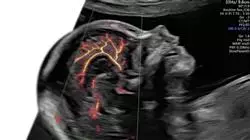

了解宫颈机能不全、胎盘早剥和绒毛膜羊膜炎的最新进展"

这个产科急救的第二和第三季度护理大学课程包含了市场上最完整和最新的科学课程。主要特点是:

- 这个课程的内容图文并茂、示意性强、实用性强为那些视专业实践至关重要的学科提供了科学和实用的信息